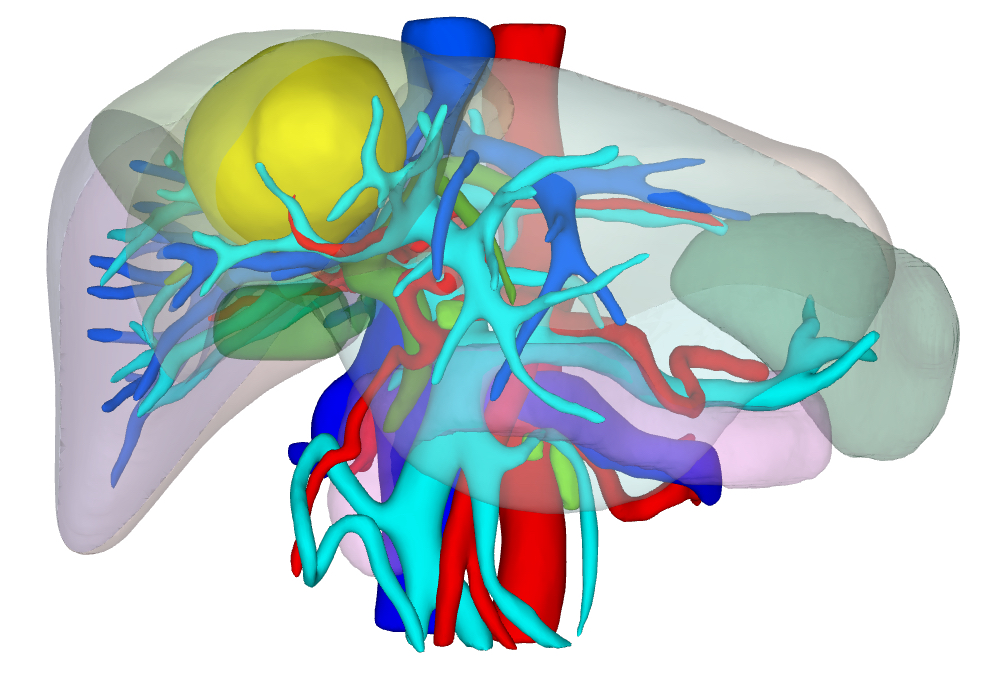

由科室副主任郭威主刀,科室副主任吴嘉兴、住院医师李伟锋组成的手术团队采用经腹腔镜荧光反染引导肝中叶(Ⅳ+Ⅴ+Ⅷ段)切除术,术后患者恢复顺利,痊愈出院。

肝胆胰外科主任姚红兵介绍,腹腔镜肝中叶切除术是肝胆外科顶尖的微创技术,曾被誉为肝胆外科腹腔镜手术的「珠穆朗玛峰」,其原因在于:1、解剖位置复杂,周围比邻重要血管,稍有不慎将会导致灾难性的后果。2、手术创面较大,术后极易出现胆漏等并发症。3、显露及操作困难,肝中叶位置较深,周围有左外叶和右后叶包裹,手术视野的暴露和操作空间非常有限。